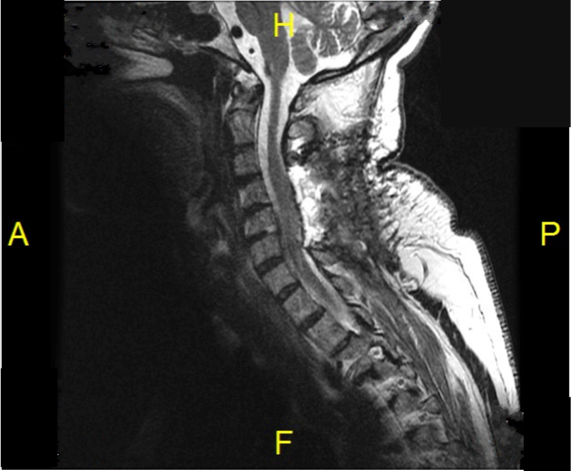

All nerve rootlets were preserved. The spinal cord was reduced to a ribbon due to chronic compression by the tumor mass, which was found by pathology to be a WHO grade I (benign) meningioma.

Post-op MRI below confirms gross total resection of the tumor with re-expansion of the spinal cord to normal contours.